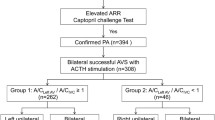

We retrospectively analyzed 154 patients diagnosed with PA and who underwent AVS at our hospital between January 2010 and June 2021. Based on machine learning, we determined predictors of PA subtypes diagnosis from the results of blood and loading tests.

The accuracy of the machine learning was 88% and the top predictors of the UPA were plasma aldosterone concentration after the saline infusion test, aldosterone to renin ratio after the captopril challenge test, serum potassium and aldosterone-to-renin ratio. By using these factors, the accuracy, sensitivity, specificity and the area under the curve (AUC) were 91%, 70%, 99% and 0.91, respectively. Furthermore, we examined the surgical outcomes of UPA and found that the group diagnosed as unilateral by the predictors showed improvement in clinical findings, while the group diagnosed as bilateral by the predictors showed no improvement.